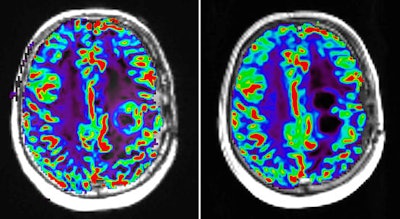

Perfusion MR image with dynamic susceptibility-weighted protocol shows activity of glioblastoma tumor before (left) and after (right) pharmaceutical therapy. Image courtesy of Image Analysis Group (IAG).The contribution of advanced imaging

Functional MRI sequences include diffusion-weighted imaging (DWI) and dynamic contrast-enhanced (DCE) MRI. DWI measures the movement of water molecules in tissue and can be used to reconstruct neuronal pathways in the brain as well as to measure cellular density. DCE-MRI uses a gadolinium-based contrast agent that changes signal intensity and, therefore, makes blood visible in the image, which is particularly beneficial in inflammatory or necrotic tissue.

Another technique, multiparametric MRI (mpMRI), is also useful for its combination of anatomical and functional sequences within one MRI setting. This enables the assessment of functional characteristics such as tumor perfusion and cellular density alongside anatomical high-resolution lesion location.